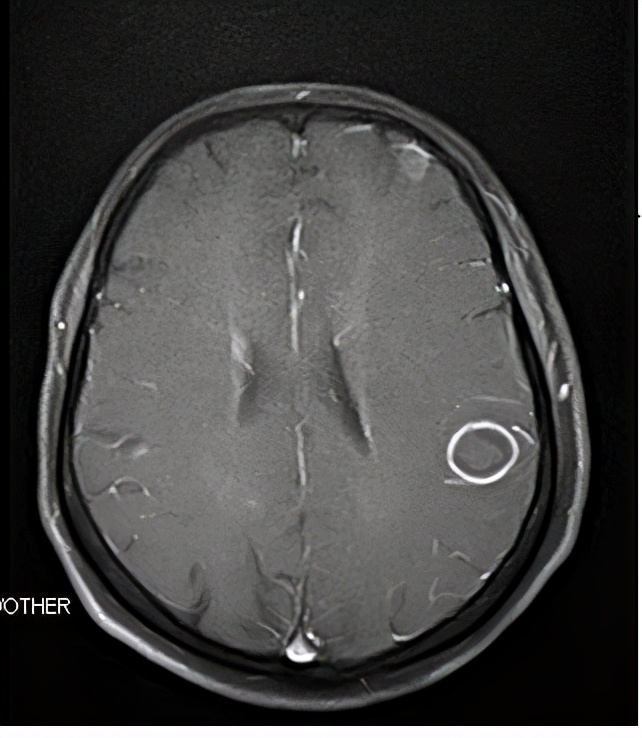

治疗过程:确诊后第3天进行经导管动脉化学栓塞治疗,也叫微创介入治疗。化学药物配伍方案为顺铂、长春瑞滨和羟基喜树碱。治疗后12小时有恶心,无呕吐,未作特殊处理。治疗后第3天出院,回家口服埃克替尼,每天3次每次125毫克,每月到门诊注射1次唑来膦酸控制骨转移。1月后复查,右肺肿瘤缩小至2厘米左右,左肺转移灶和肝转移灶基本消失。继续使用埃克替尼和唑来膦酸巩固治疗。患者行动自如,KPS评分100分,平时在家做家务,照看孙子。之后每3月复查一次,病情稳定。2年后,2015年3月,突然头晕,脑磁共振检查发现多个直径1到2厘米转移病灶。再次右肺穿刺活检基因检测发现T790M点位突变。停用埃克替尼,改用奥西替尼口服,每日1次80毫克。复查脑磁共振,1月后转移灶稳定,3月后出现中心坏死,半年后转移灶大部分消失,最大的一个几乎成为空壳。继续维持治疗4年,孙子也上学前班了。2019年初,家属打听到一种“新药”和“特效疗法”,就停止原有治疗,去吃“新药”和全身按摩。3月后体力明显下降,逐渐卧床不起,肿瘤再次开始扩散,患者及家属放弃希望,回乡看望众亲友后而终。

2年后出现脑多发转移(磁共振)

改变治疗方案后脑转移明显缓解(磁共振)